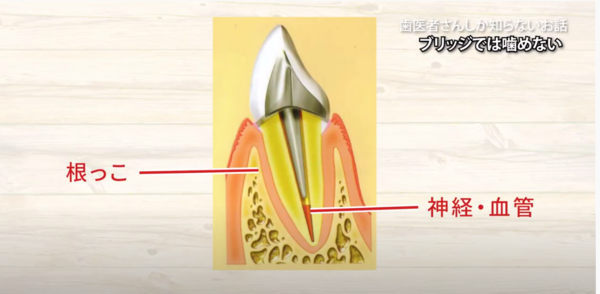

断面で見ると

中が綺麗になりますので

その後です

被せものをしようとするのですけれど

安定しませんね

ですので

今度は

杭のようなものを作り

この杭を穴の中に差し込みます。

そうしますと

この杭の頭の部分が

上に出てきますので

これを土台にして

帽子をかぶせる

という治療が多く見受けられます。

根っこがあって

中に神経、血管

そして

代りにお薬が入っていますから

このお薬

芯棒

被せ物が

同一直線状にあります。